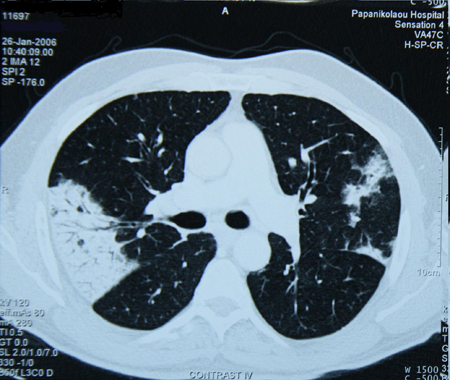

Assessment of persistent pulmonary infiltrate

Chest CT scan of a patient with amiodarone pulmonary toxicity, showing asymmetric opacities with a peripheral distribution

From the collection of Athanasia Pataka, MD